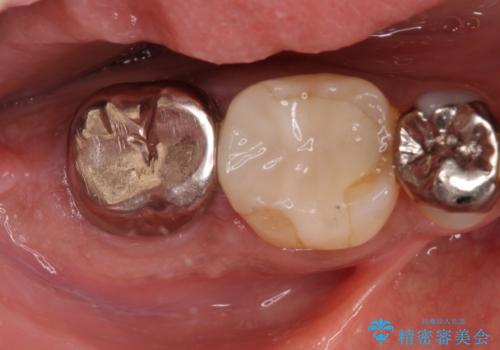

抜歯後十分な骨の回復が認められず、単独の骨増生を行った後にインプラントを埋入しました。

インプラント埋入時に骨が足りない場合にはインプラント埋入前に骨増生を行います。また、インプラント周囲の角化歯肉が不足した場合は角化歯肉の移植も行うことがあります。

どちらの治療もインプラントの長期予後を高めるために必要な治療です。